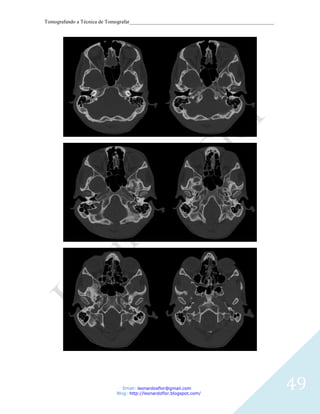

Imagem 1

Corte axial. 1, Cavidade orbitária. 2, Seio frontal. 3, Osso esfenóide

Imagem 2 - Corte axial. 1, Globo ocular. 2, Septo nasal. 3, Células etmoidais. 4, Seios

esfenóidal. 5, Hipófise. 6, Dorso sellae.

Imagem 3

Corte axial. 1, Globo ocular. 2, Septo nasal. 3, Células etmoidais. 4, Seios esfenóidal. 5,

Clivus.

Imagem 4

Corte axial. 1, Seio maxilar esquerdo. 2, Canal nasolacrimal. 3, Concha. 4, Septo nasal. 5,

Arco zigomático. 6, Processo condilar da mandíbula.

Imagem 5

Corte axial. 1, Concha. 2, Seio maxilar. 3, Asa lateral do processo pterigóideo. 4,

Nasofaringe. 5, Atlas (C1). 6, Fenda do palato ptérigo.

Imagem 6

Corte axial. 1, Seio maxilar. 2, Apófisis pterigoides,. 3, Nasofaringe. 4, Mandíbula. 5, Arco

45

anterior do atlas. 6, dente do áxis (Processo odontoide).